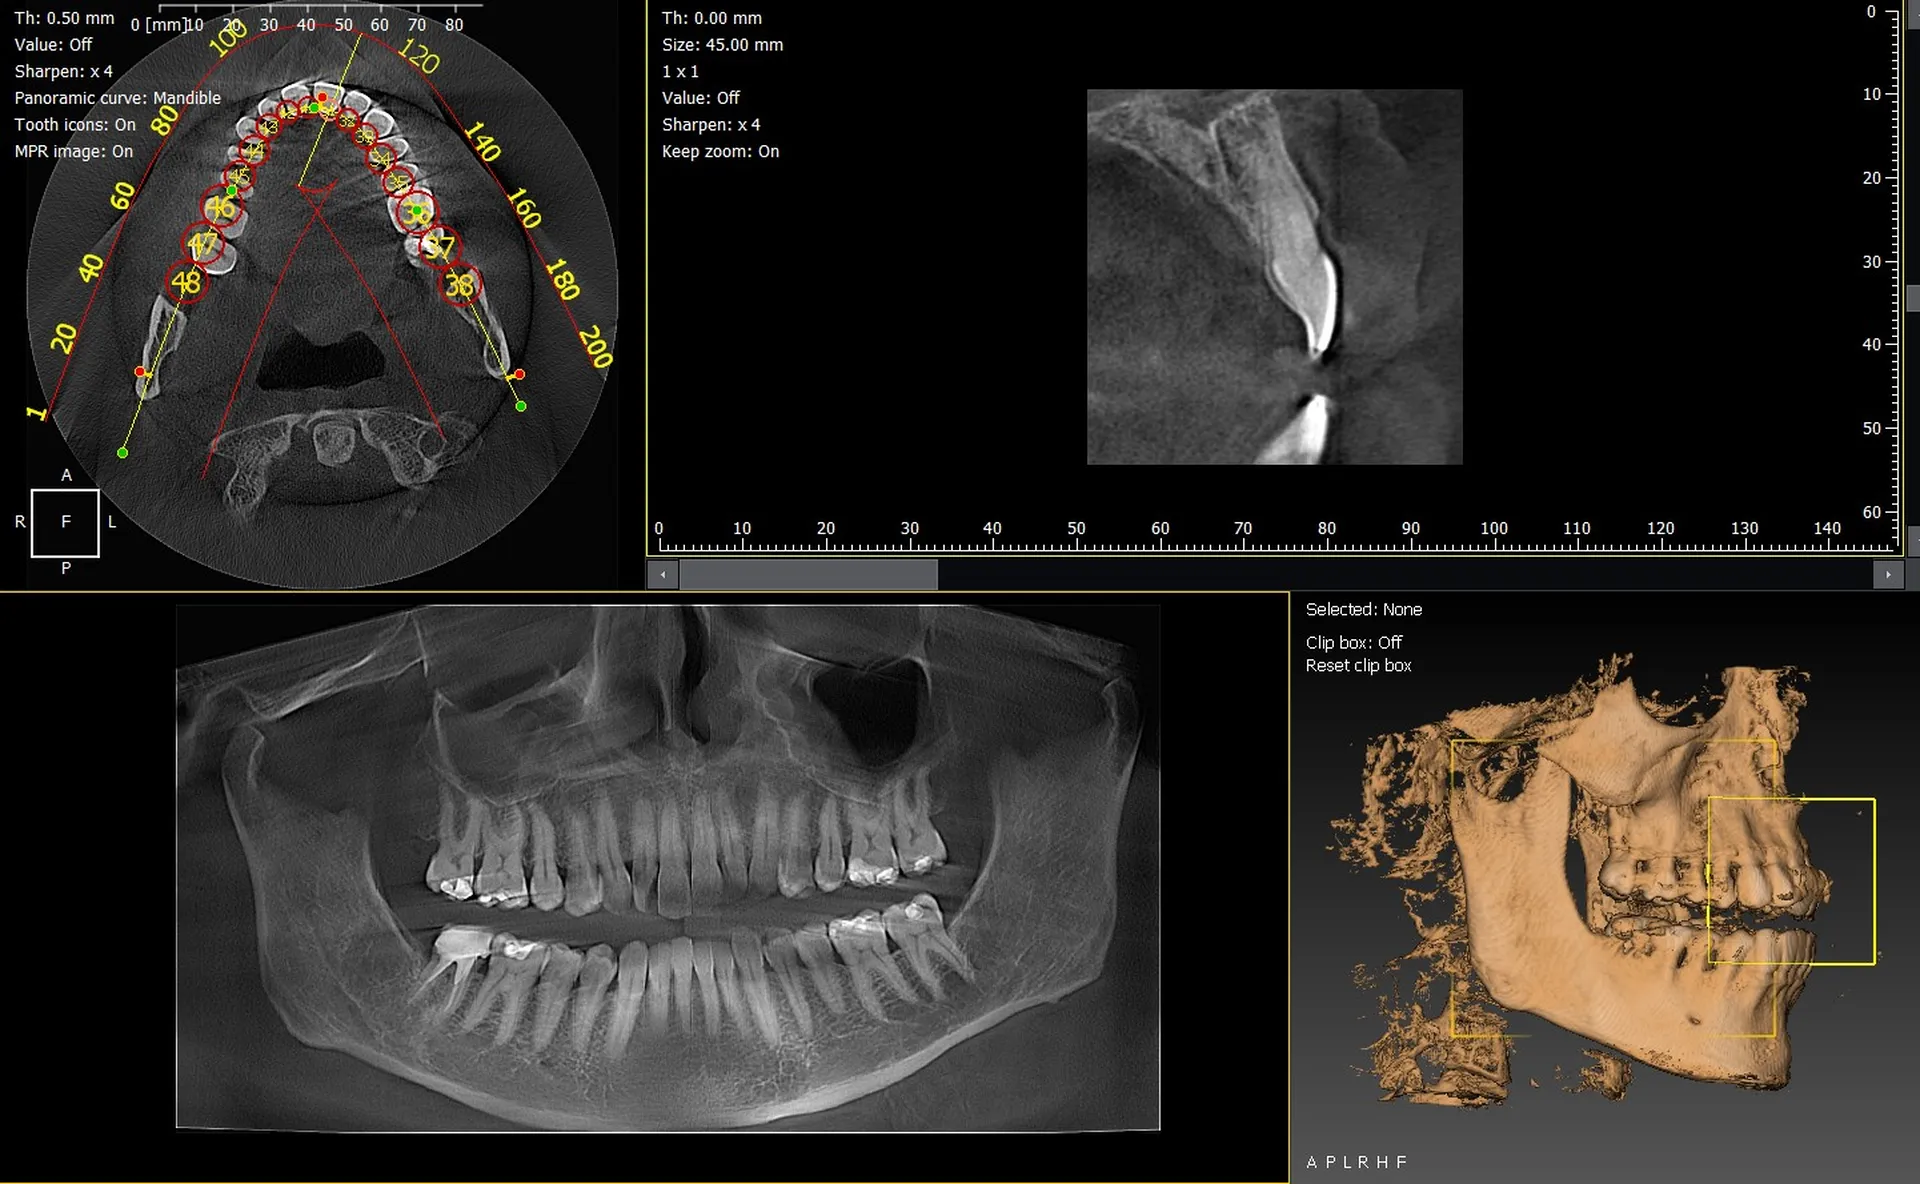

Les cabinets dentaires de Gap et des Hautes Alpes 05 recherchent des équipements d’imagerie fiables et précis pour optimiser leurs diagnostics et leurs plans de traitement. Les systèmes panoramiques 3D CBCT offrent aujourd’hui une vision détaillée des structures osseuses et dentaires, indispensable en implantologie, endodontie, orthodontie et chirurgie orale. Parmi les solutions les plus performantes, les gammes Durr Dental VistaVox et Owandy I-Max 3D se démarquent par leur qualité d’image, leur ergonomie et leur facilité d’intégration dans les cabinets gapençais.

Durr Dental VistaVox : un panoramique CBCT pensé pour la précision clinique

Le VistaVox est reconnu pour son volume d’acquisition optimisé permettant une analyse complète de l’arcade. Son imagerie haute définition facilite l’étude du nerf mandibulaire, des sinus et des zones complexes.

• Volume 3D couvrant l’ensemble de l’arcade.

• Haute résolution avec faible dose de rayonnement.